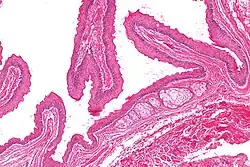

| Micrograph of a steatocystoma showing the characteristic corrugated eosinophilic lining. H&E stain | |